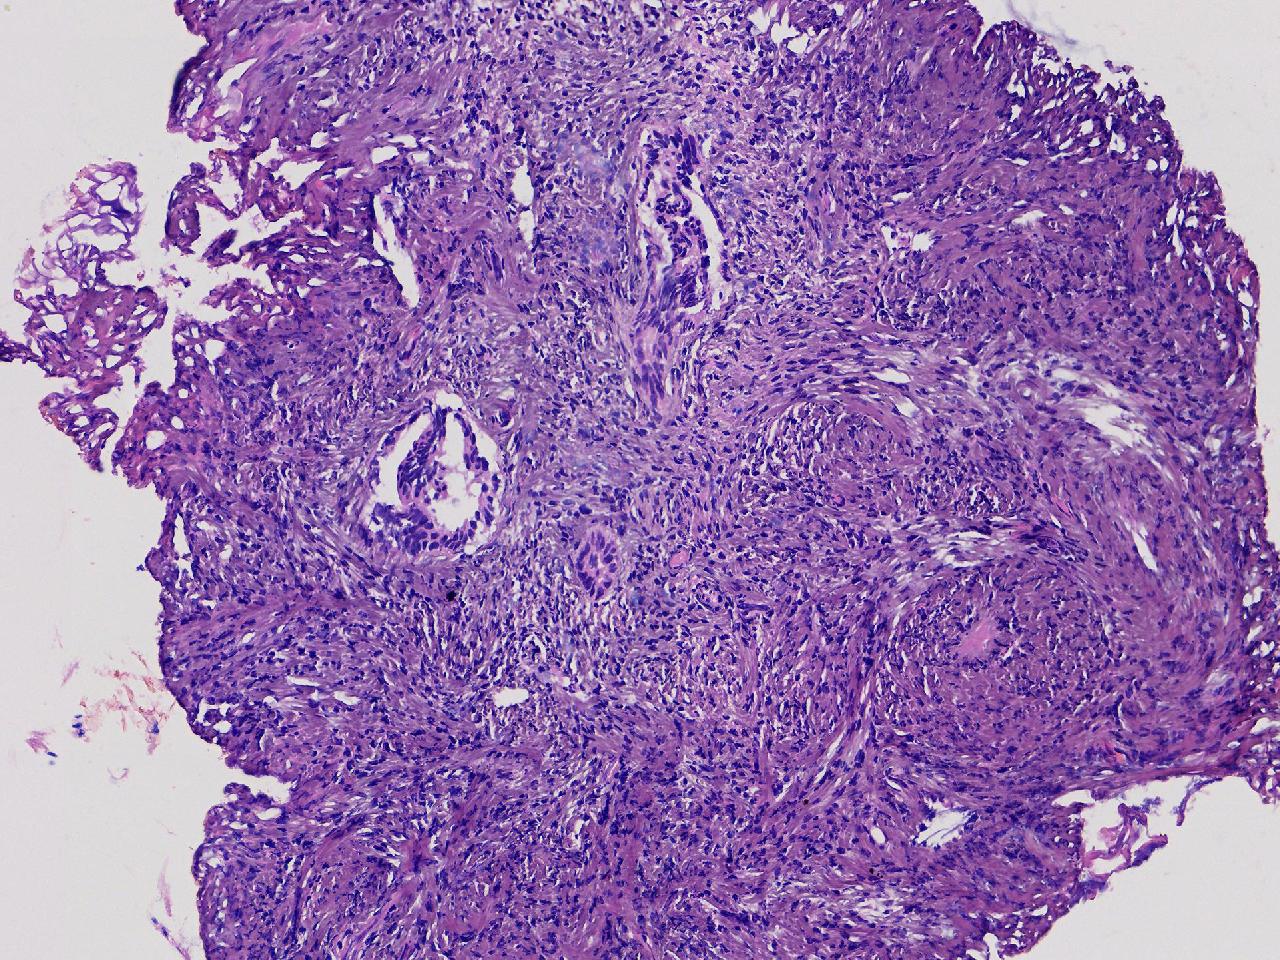

性别

女

年龄

56岁

彩超示宫腔内见5x3ml的团状偏强回声结节,边界清。

宫腔息肉?

灰粉色不整形软组织多块,0.5X0.3X0.3厘米。

首先考虑子宫内膜息肉,有些区域间质细胞较密,找找看有没有核分裂。

彩超提示强声团体积不小,待完整切除送检再综合诊断。